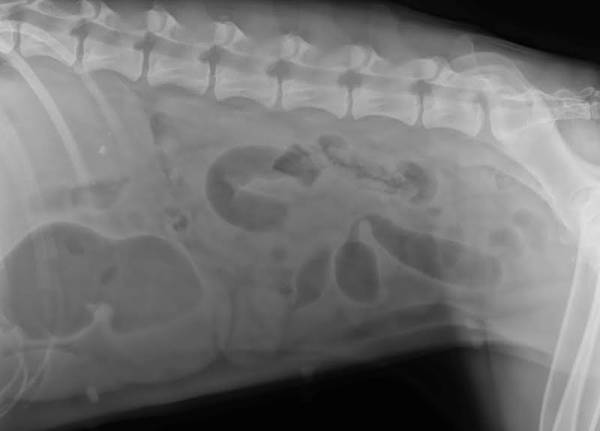

So...I lost my other post. Just wanted to update for those who care. To recap: Eden was hospitalized yesterday for suspected intestinal blockage.

I figured it might be "fun" to post these films and see what everyone thinks/diagnoses and then I'll share the outcome. These were taken upon admittance. Next, I'll post the ones taken an hour and a half after fluids were administered.

I think I see gas bubbles; is her stomach trying to flip or ?? Scarey looking to me as I really don't know what I am looking at. Please share if you can, and I hope she is OK. Nan

Enlarged spleen?? A piece of a dog collar; a part of a dog clip?? Can't tell. Looks like trouble to me.

The one x-ray that appears to be a top view shows an obvious enlargement on the ride side. It appears to me that there is some foreign matter going on. Stomach flip as Nan said...I can see that too.

3 vets at first hospital saw these, and the 1 vet I sent them to saw them. All saw obstructive pattern, albeit unclear as far as the nature of the obstruction. I'm extremely careful about what the dogs have access to, but Eden is a trouble-maker. She loves to grab something out of the hamper on her way out the backdoor through the laundry room. I find my son's clothes outside regularly- she's just sneaky enough to turn her head so we don't notice what she's got in her mouth. If any of mine are going to eat something stupid, it's Eden.

I posted these xrays because they were foolers.